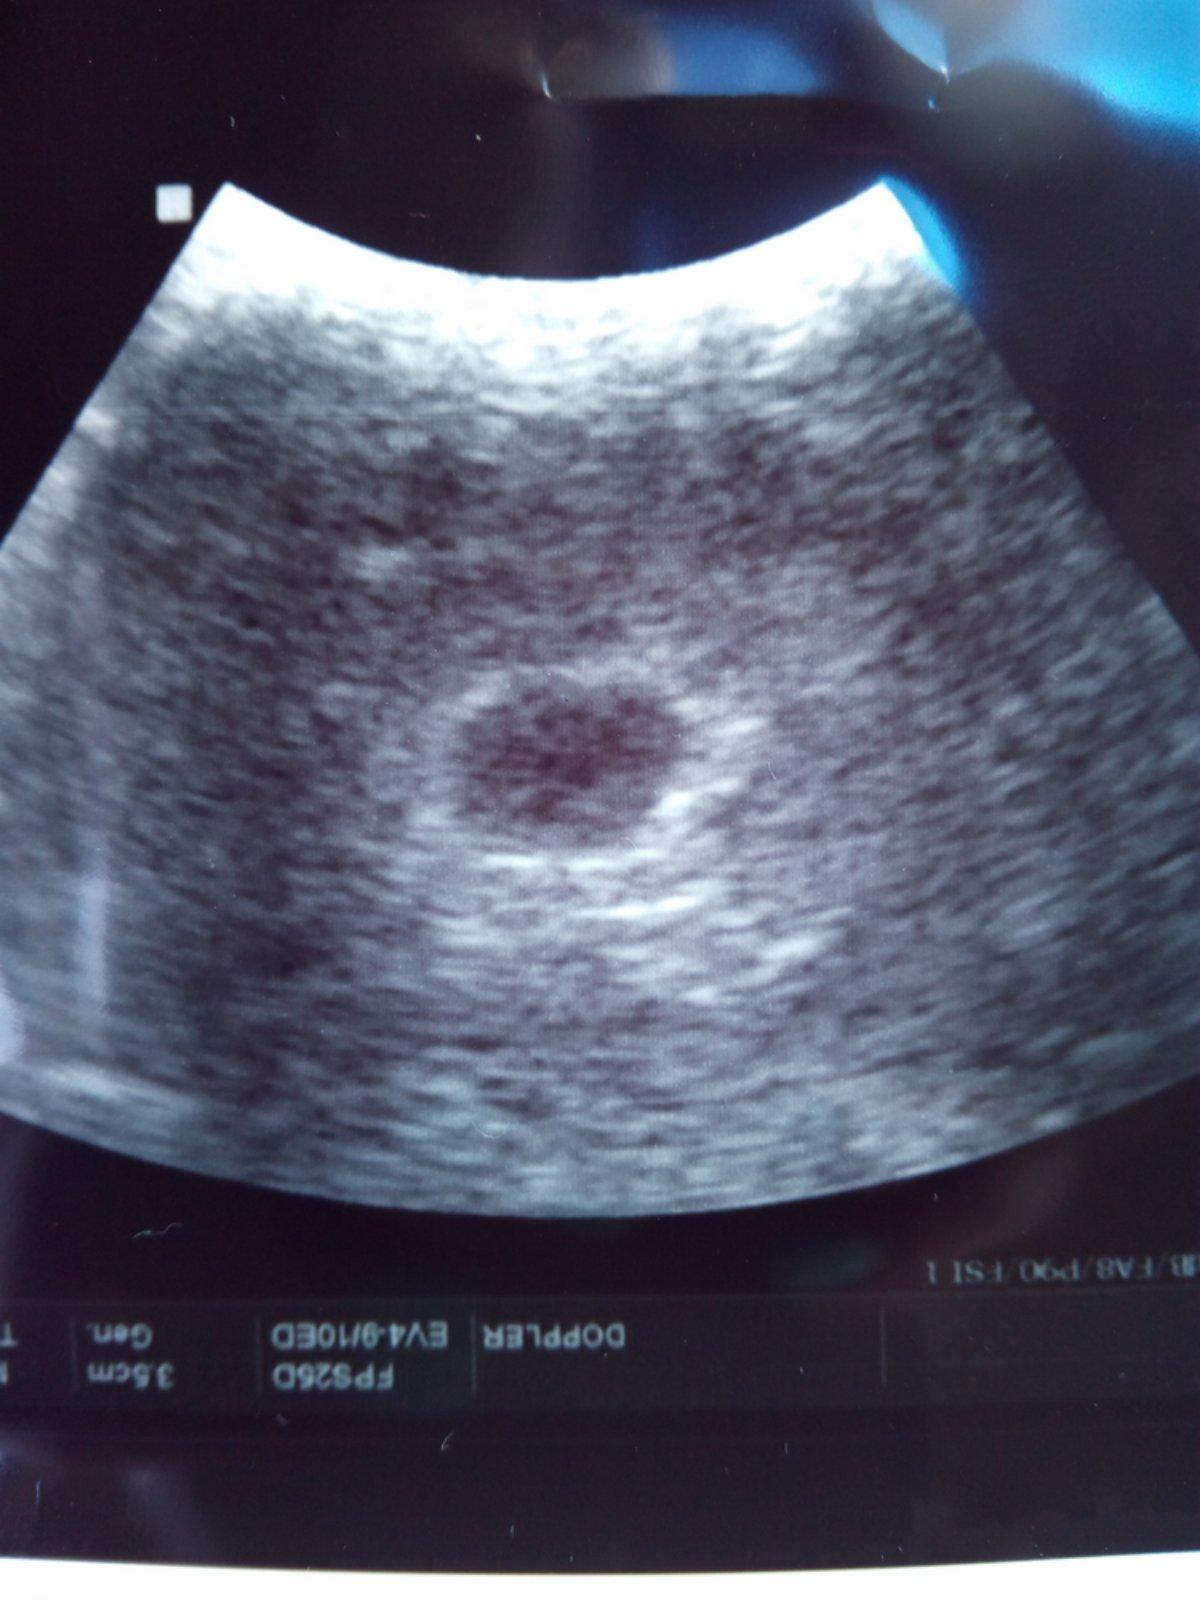

Holky, myslete, prosím dneska na mě, jdu na UTZ, doufám, že dr aspoň něco uvidí. To, co jsem si tu dneska přečetla a ještě v jiné skupině mi moc nepřidalo, cítím se mizerně.